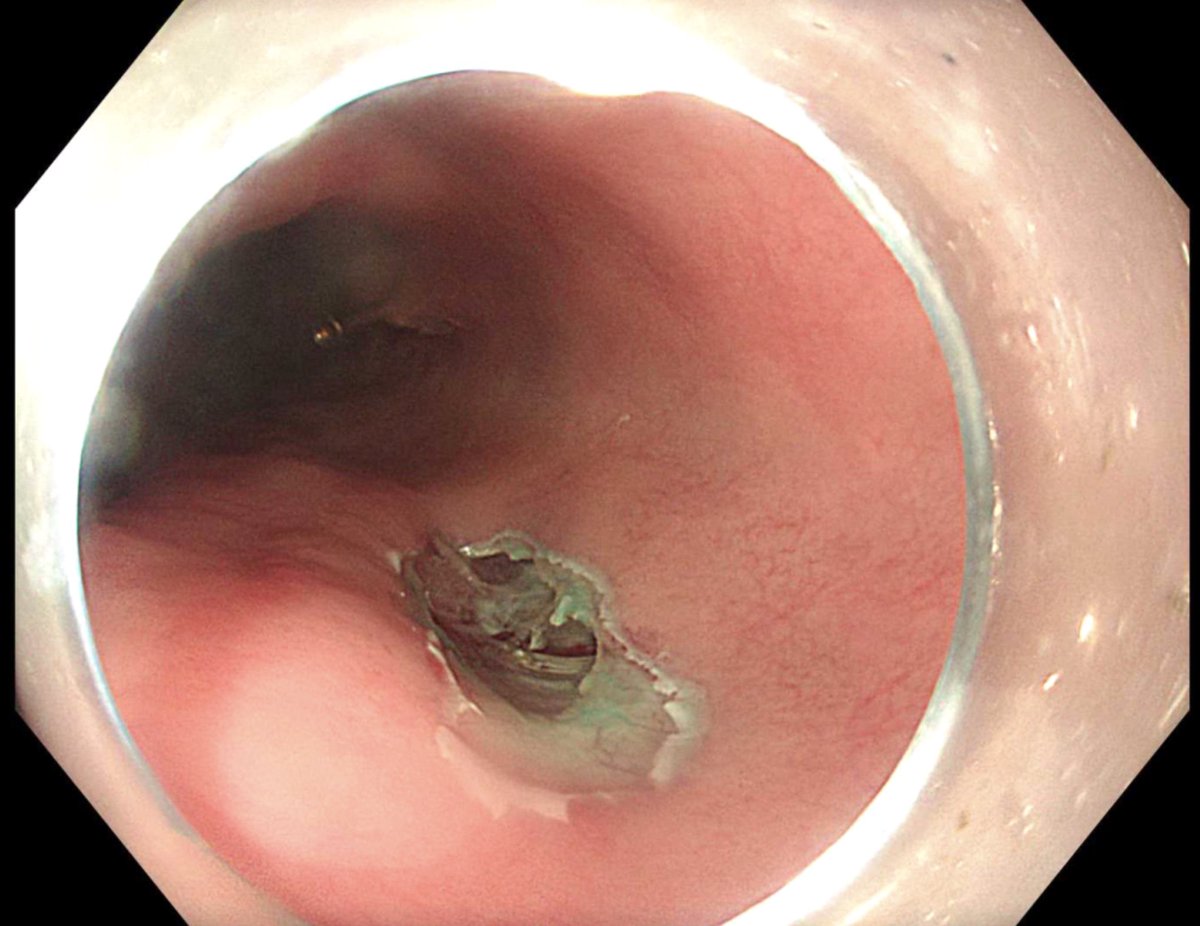

هذه صور لاحدى الحالات التي اجريت في المستشفى الجامعي و التي بحمد الله تكللت بالنجاح بواسطة المنظار عن طريق اجراء فتحة صغيرة لا تتجاوز ٢ سم في المريء.